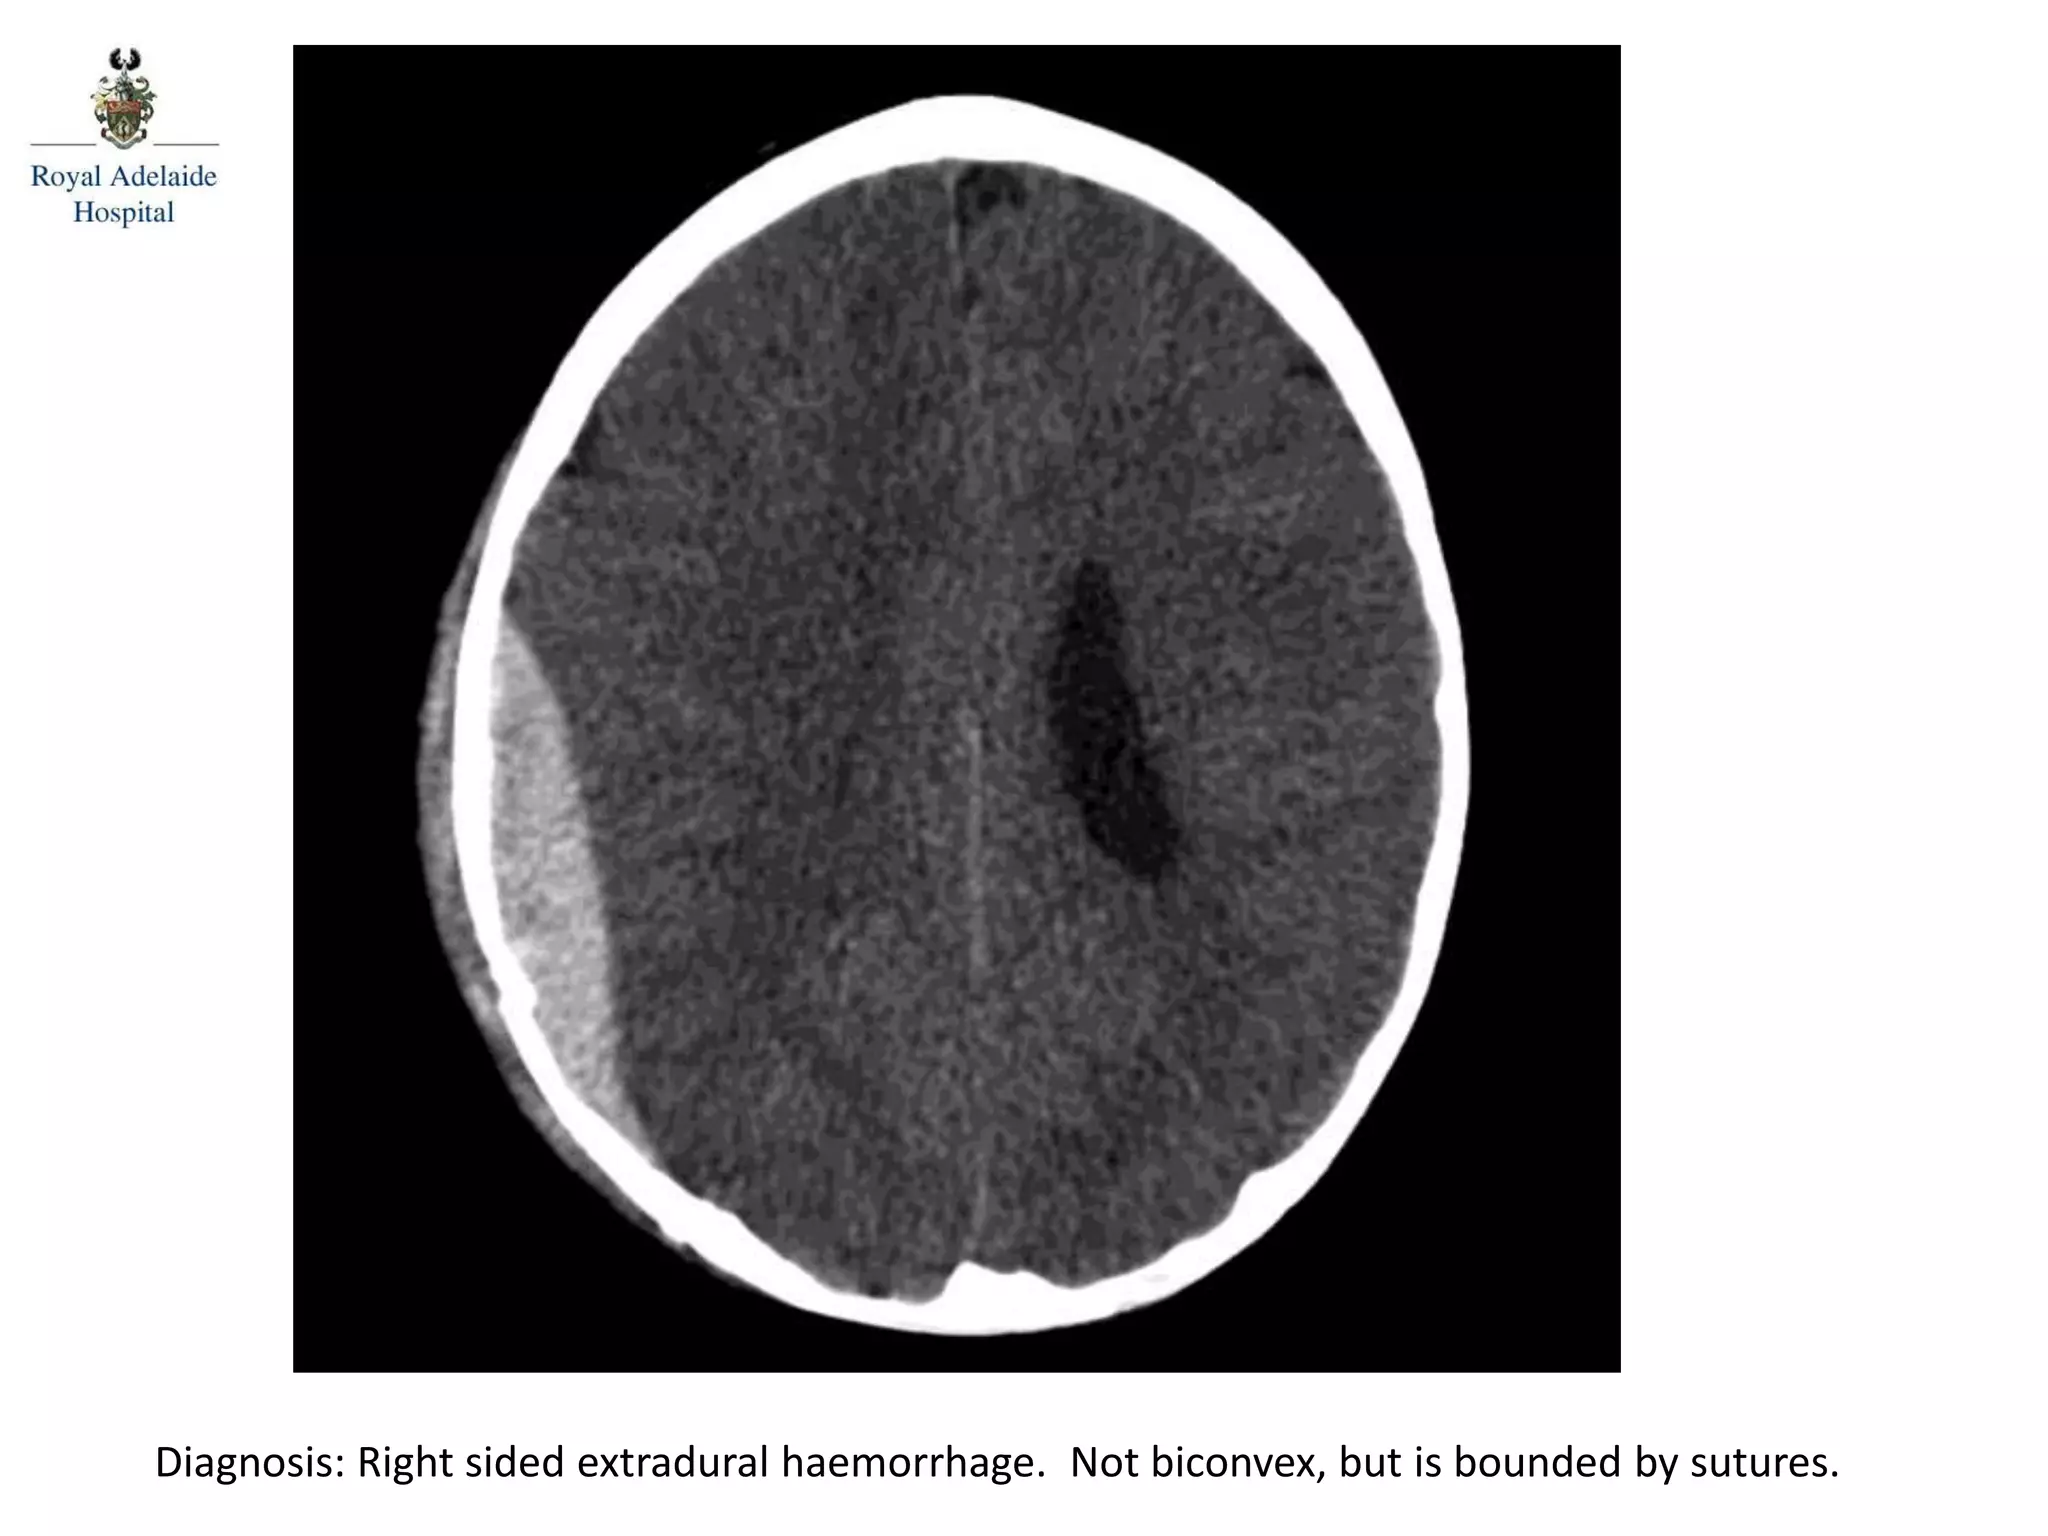

The document outlines multiple diagnoses from head CT cases, including small left basal ganglia bleed likely due to hypertension, various types of subdural and subarachnoid hemorrhages, and evidence of hydrocephalus. It details traumatic origins of some hemorrhages and notes obstructing masses and atrophic changes. Overall, there are significant findings indicating complications related to cerebral hemorrhages and ventricular enlargement.